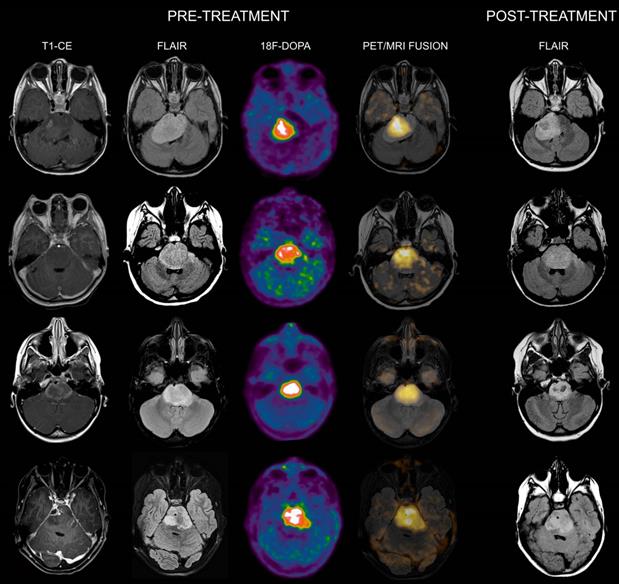

When evaluating the association between 18F-DOPA uptake tumor volume at admission with the MRI tumor volume at maximum response, areas of increased tracer uptake corresponded to regions with more prominent residual components/lack of response following treatment in all patients. Representative images of DIPGs at admission and following first-line ChT-RT are reported in Figures 1 and 2.

Figure 2

Co-registered and fused MRI and 18F-DOPA PET images of DIPGs with T/S > 1. First row: 4-year-old female. Pre-treatment contrast-enhanced (CE) T1-weighted imaging showed ring enhancement. MRI tumor volume was 40 cc. 18F-DOPA PET and fused 18F-DOPA PET/MRI revealed markedly increased uptake (T/S 1.09) with a PET tumor volume of 21 cc, corresponding to a uniformity of 52.5%. Post-treatment FLAIR demonstrated an MRI tumor volume of 28.9 cc. Overall survival (OS) was 9 months. Notice the coincidence between the tumoral component with increased uptake and the residual lesion, and the tumor volume reduction in the left ventrolateral pons corresponding to absence of increased uptake. Second row: 7-year-old male (anaplastic astrocytoma, H3K27M-mutant). Pre-treatment CE T1-weighted imaging did not reveal areas of ring enhancement. MRI tumor volume was 34.06 cc. On 18F-DOPA PET and fused 18F-DOPA PET/MRI the T/S was 1.27, the tumor volume 25 cc, and the uniformity 73.39%. Following treatment, the MRI tumor volume was of 33.7 cc. OS was 10 months. Third row: 10-year-old female. On pre-treatment CE T1-weighted imaging there was extensive ring enhancement. MRI tumor volume was 26 cc. On 18F-DOPA PET and fused 18F-DOPA PET/MRI the lesion presented a T/S of 1.7 and a tumor volume of 18 cc, corresponding to a uniformity of 69.23%. Post-treatment FLAIR image demonstrated an MRI tumor volume of 20 cc. OS was 6 months. Fourth row: 10-year-old male (glioblastoma, H3K27M-mutant). Pre-treatment CE T1-weighted imaging revealed a right focal area of ring enhancement. MRI tumor volume was 46 cc. 18F-DOPA PET and fused 18F-DOPA PET/MRI demonstrated markedly increased uptake (T/S 2.32) and a tumor volume of 31 cc, corresponding to a uniformity of 67.39%. Following treatment, the MRI tumor volume was 42 cc. OS was 6 months.